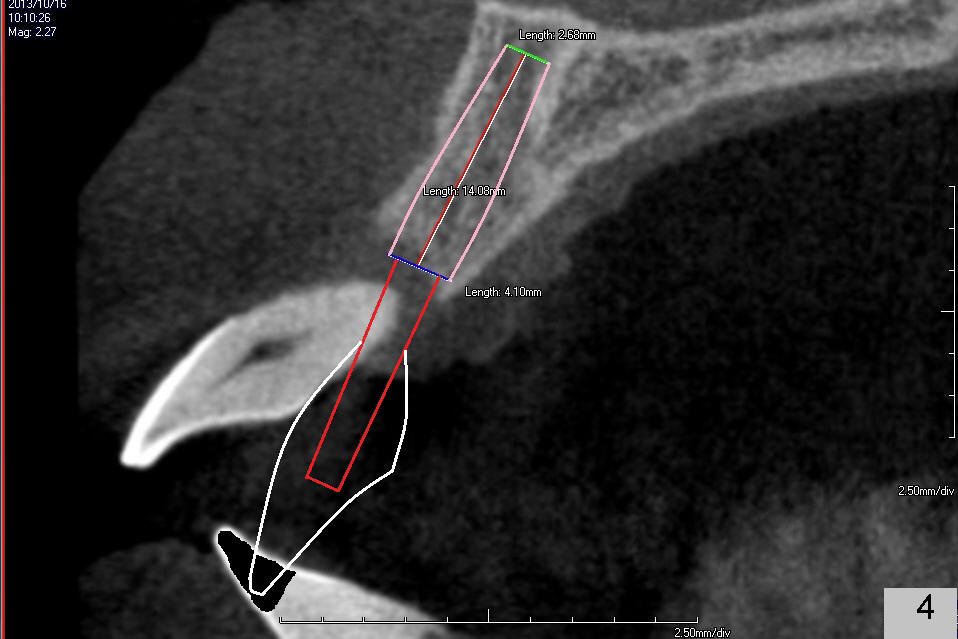

A 49-year-old man has severe chronic periodontitis. The upper central incisors are protrusive and mobile (Fig.1,2: #8,9), but the basal bone is wide and tall (BB in Fig.2). Immediate implants are going to be placed. To avoid malpositioning of the implant, initial osteotomy begins close to the palatal plate (Fig.3: P), while the axis of the osteotomy is parallel to and close to the buccal plate (>). The implant (Fig.4 pink), abutment (red) and the crown (white) will be in a favorable trajectory. To reduce protrusion, the incisal edge of the lower central will be trimmed (compare Fig.3 * and Fig.4 black area).